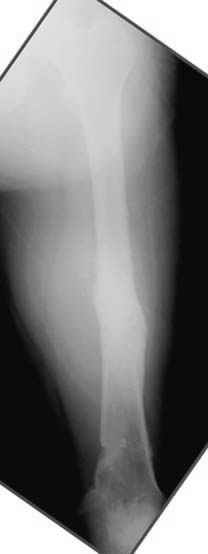

пластическая модель; и коррекция бедра аппаратом Илизарова.

Имею другие снимки тоже, получится как отчет о моей работе.

хотя даже если бы и инфекция , то nail exchange с рассверливанием канала - вариант дебрайдмента) Я думаю, что последовательность развития событий:

Узкий к-м канал - тонкий гвоздь- усталостный перелом дистальных винтов - развитие нестабильности и как ее результат остеолиз вокруг гвоздя - деформация анатомической оси бедра. Похоже, что я понял почему аппарат, а не новый гвоздь:-)